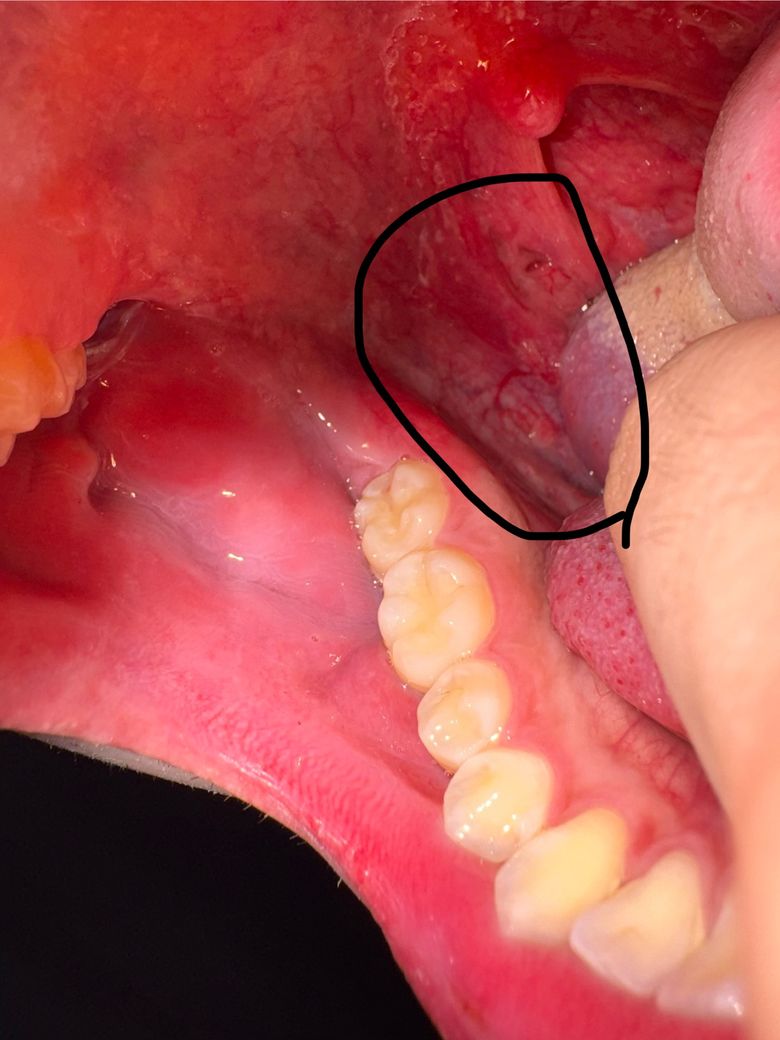

입 안쪽 혓바닥 아래에 핏줄이 터진 것 처럼 되어있고 종기? 뾰루지 처럼 작은 무언가가 있습니다 이물감이나 통증은 전혀 없는데 우현히 발견하여 혹여 큰 질환이 될까 걱정되서 질문드립니다 사진상으로는 그냥 동그랗게 뭥가 난것처럼 보이지만 실제로는 살점이 위로 솟은 듯한 느낌입니다 큰 문제가 아니라면 좋겠습니다

• 1번 째 사진

• 사진상 위치는 혀 옆면 하부, 구강저 부위로 보이며, 점막이 약간 돌출되고 주변 혈관이 확장되어 보입니다. 통증이나 이물감이 없는 점을 고려하면 급성 염증성 병변보다는 양성 변화 가능성이 높습니다.

가장 흔한 원인은 다음과 같습니다. 첫째, 점액낭종으로 침샘관이 막히거나 손상되면서 점액이 고여 작은 혹처럼 보일 수 있습니다. 무통성이고 투명하거나 붉게 보일 수 있습니다. 둘째, 국소 혈관 확장 또는 경미한 점막하 출혈입니다. 혀를 씹거나 자극이 반복되면 혈관이 도드라져 보이거나 멍처럼 보일 수 있습니다. 셋째, 섬유성 증식으로 반복 자극에 의해 살짝 솟은 조직이 생기는 경우입니다.